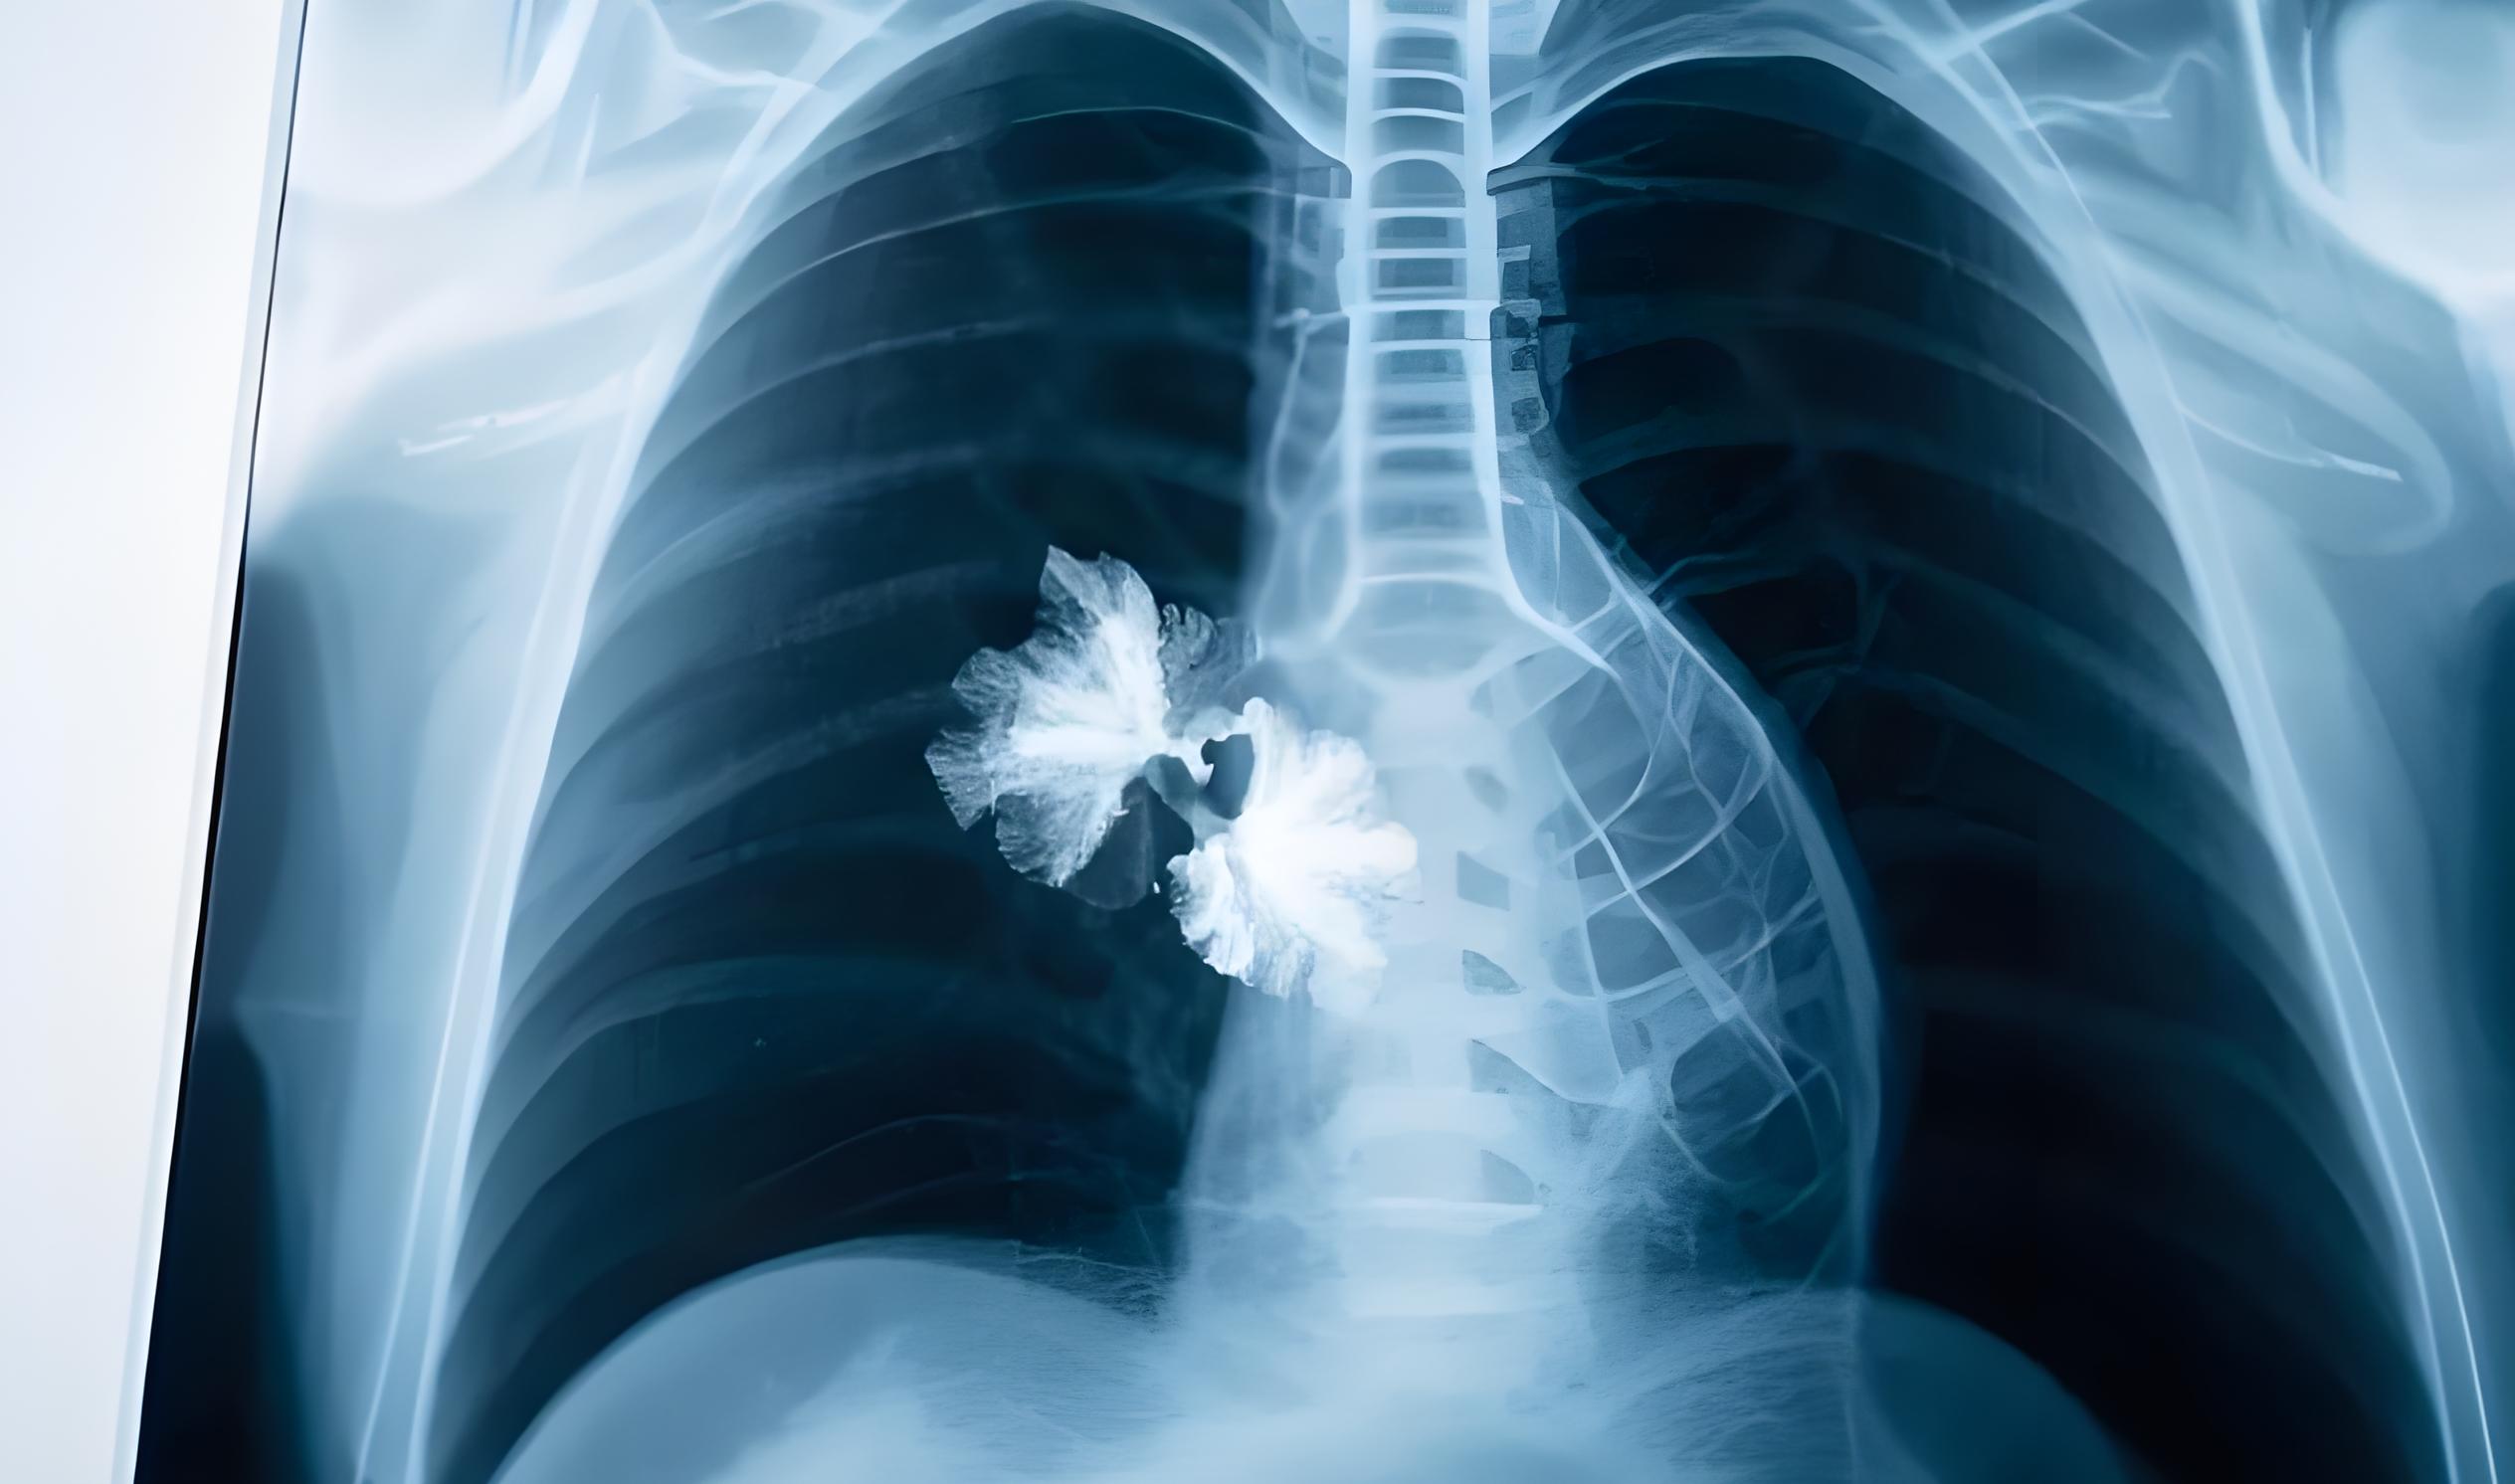

近年來,肺結節問題愈發嚴峻,已成為全球矚目的公共健康難題。

據《Cell》雜志最新權威研究,全球肺結節患者人數增長超60%。《健康概覽》報告顯示,截至2024年3月,全球患病人數超15億,中國就有5.2億。

《國民健康白皮書(2024版)》指出,我國肺結節檢出率達55.9%,近乎每十人中就有六人面臨此健康風險,后疫情時代,肺結節的威脅不容小覷。

肺結節或許是肺癌的早期信號,早干預治愈率越高。